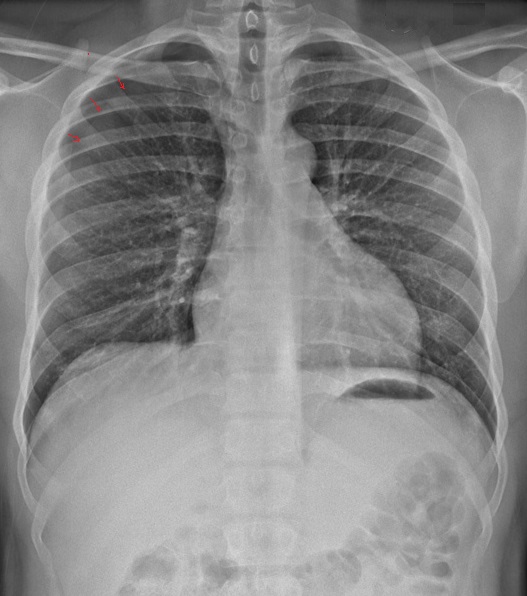

Meme cas à

exposant au temps de expiration . On

peut en s'observe le pneumothorax à

petit volume collecte à l'apex et à

region axillaire droit du poumon |